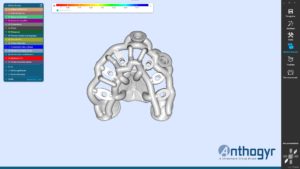

Merci au Dr Bailly et à la société Anthogyr pour cet article.

4 ème étape : impression du bridge provisoire en résine, nettoyage et collage sur embase titane.

5ème étape : bridge provisoire posé en bouche